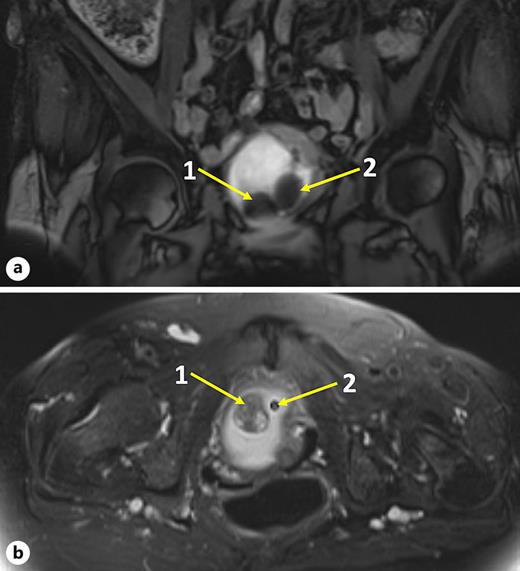

Physical examination revealed no flank masses. Abdominal ultrasound raised the suspicion of a bladder lesion. Urinalysis revealed no white cells or bacteria in the stained urinary sediment. A magnetic resonance imaging of the pelvis and abdomen revealed a sessile bladder mass (2.8 cm) at the bladder trigone on the right side, without perivesical infiltration or regional lymphadenopathy described as leiomyoma, as shown in Figure 1. Cystoscopy revealed the suspected bladder leiomyoma and an obstructed anterior bladder neck with a large mass located from a “7 o’clock” to “11 o’clock” area. Typical redness of the tissue was detected because of the indwelling urinary catheter. The photodynamic diagnosis was negative, as shown in Figure 2b.